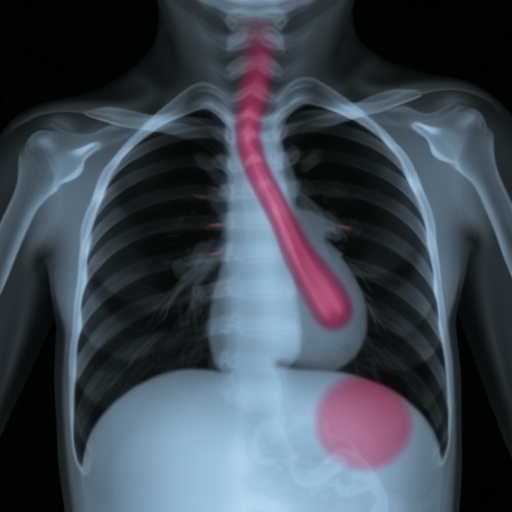

Pulmonary aplasia is an extremely rare condition characterized by the absence of a lung and its accompanying structures. In this particular case, the left lung was absent, with the left pulmonary artery also being undeveloped. The child, primarily studied in a medical facility in Nepal, exhibited significant clinical signs indicative of respiratory compromise, emphasizing the urgent need for early detection and intervention in similar scenarios.

Diagnostic imaging plays an instrumental role in affirming the diagnosis of pulmonary aplasia and agenesis. In this case, advanced imaging techniques such as high-resolution computed tomography (HRCT) allowed for a detailed assessment of the pulmonary architecture, substantiating the observations of anatomical anomalies. The use of such imaging modalities is crucial for forming an appropriate management plan that addresses both the immediate and long-term needs of affected children.